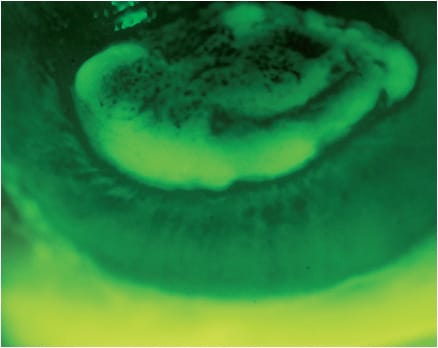

Another way to detect edema is by noting the presence of negative staining over the cornea when stained with sodium fluorescein (Figure 7). Decreased BCVA, steepening in corneal curvature, and increase in corneal thickness are other objective measures that can be used to corroborate and confirm the diagnosis.4